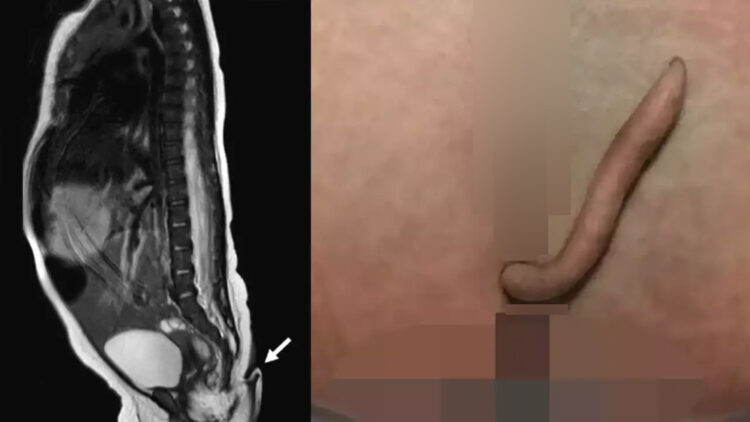

5.7 സെന്റിമീറ്റർ നീളമുള്ള വാലാണ് കുഞ്ഞിനുള്ളതെന്ന് ഡോക്ടർമാർ സാക്ഷ്യപ്പെടുത്തുന്നു. ലോകത്ത് ഇതുവരെ 200ൽ താഴെ മാത്രമാണ് ഇത്തരത്തിൽ രേഖപ്പെടുത്തിയിട്ടുളളത്.. മെക്സിക്കോയിൽ റെക്കോർഡ് ചെയ്യപ്പെടുന്ന ആദ്യത്തെ സംഭവമാണിതെന്നും ഡോക്ടർമാർ പറയുന്നു.

വളരെയധികം മിനുസമുള്ള, അറ്റം കൂർത്ത വാലാണ് കുഞ്ഞിന് കാണപ്പെട്ടത്. കുഞ്ഞിന് മറ്റ് ആരോഗ്യപ്രശ്നങ്ങളില്ലെന്നും ഡോക്ടർമാർ വ്യക്തമാക്കി. ഡോക്ടർമാർ ചെറിയൊരു സൂചി കൊണ്ട് വാലിൽ കുത്തി നോക്കിയിരുന്നു. കുഞ്ഞിന് വാൽ അനുഭവപ്പെടുന്നുണ്ടോയെന്ന് അറിയാനായിരുന്നു ഇത് ചെയ്തത്. ഇപ്രകാരം ചെയ്തപ്പോൾ കുഞ്ഞ് കരഞ്ഞുവെന്ന് ഡോക്ടർമാർ അറിയിച്ചു,.

പേശികളും രക്തക്കുഴലുകളും ഞരമ്പുകളുമെല്ലാം അടങ്ങുന്നതായിരുന്നു വാൽക്കഷ്ണമെന്ന് പരിശോധനയിലൂടെ കണ്ടെത്തി. അതേസമയം വാലിൽ എല്ല് ഇല്ലെന്നും ഡോക്ടർമാർ പറയുന്നു. സാധാരണ മൃഗങ്ങൾക്ക് ഉണ്ടാകുന്ന വാലിന് സമാനമായത് തന്നെയാണ് കുഞ്ഞിനുമുണ്ടായിരുന്നത്.